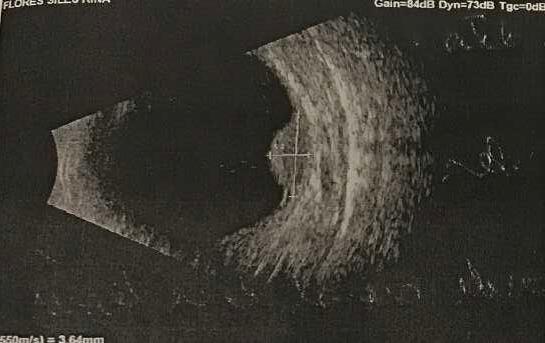

3.A. MELANOMA COROIDEO

Caso aportado por Dra. María José Vergara

ü Desprendimiento de vitreo posterior

ü Desprendimiento de retina focal inferior exudativa

ü Se constata lesion nasal 3hrs, forma de cupula cuyos diámetros máximos son:

-Al corte longitudinal: Base: 10.85nm, altura 2.58nm

-Al corte transversal: Base 8.81nm; altura 3.64nm con elementos de vascularidad

ü Es un tumor de celularidad densa, lo que se traduce en una ecogenicidad media– baja, estructura interna homogénea y gran atenuación. Es por ello que se aprecia el denominado ángulo kappa en el modo A, en el que aparece un primer piso alto correspondiente a la retina con una disminución marcada de los ecos posteriores y sombra posterior en eco B.

ü Característicamente presenta un alto flujo vascular en la base, por lo que aparecen <<flickering spikes>>. También es típica la excavación coroidea expresada como una baja ecogenicidad en la base del tumor

ü La ecografía es una técnica que también nos permite valorar, con una gran sensibilidad, la extensión extraescleral de un melanoma uveal. Para que esta pueda ser detectada debe ser igual o superior a 1.5mm, apreciándose un área vacío ecogénico bien delimitado, homogéneo, adyacente a la masa intraocular

ü La ecografía también nos permite valorar la presencia de un desprendimiento de retina seroso que habitualmente se extiende desde el margen tumoral hacia la zona ocular inferior